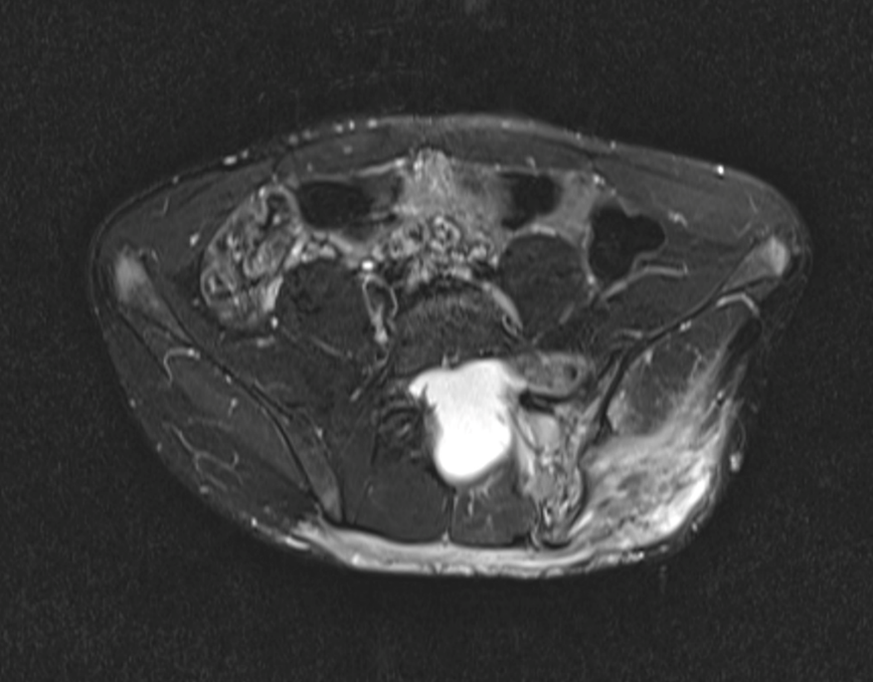

Charly is a 17-year-old student with neurofibromatosis type 1 (NF1). In childhood, he was closely monitored for a local diffuse plexiform neurofibroma (PN) of the left sacroiliac joint and back. He was lost to follow-up during puberty, experiencing school difficulties and frustration with frequent medical visits.

- MRI: diffuse PN of the lower back with infiltration of the sacroiliac joint